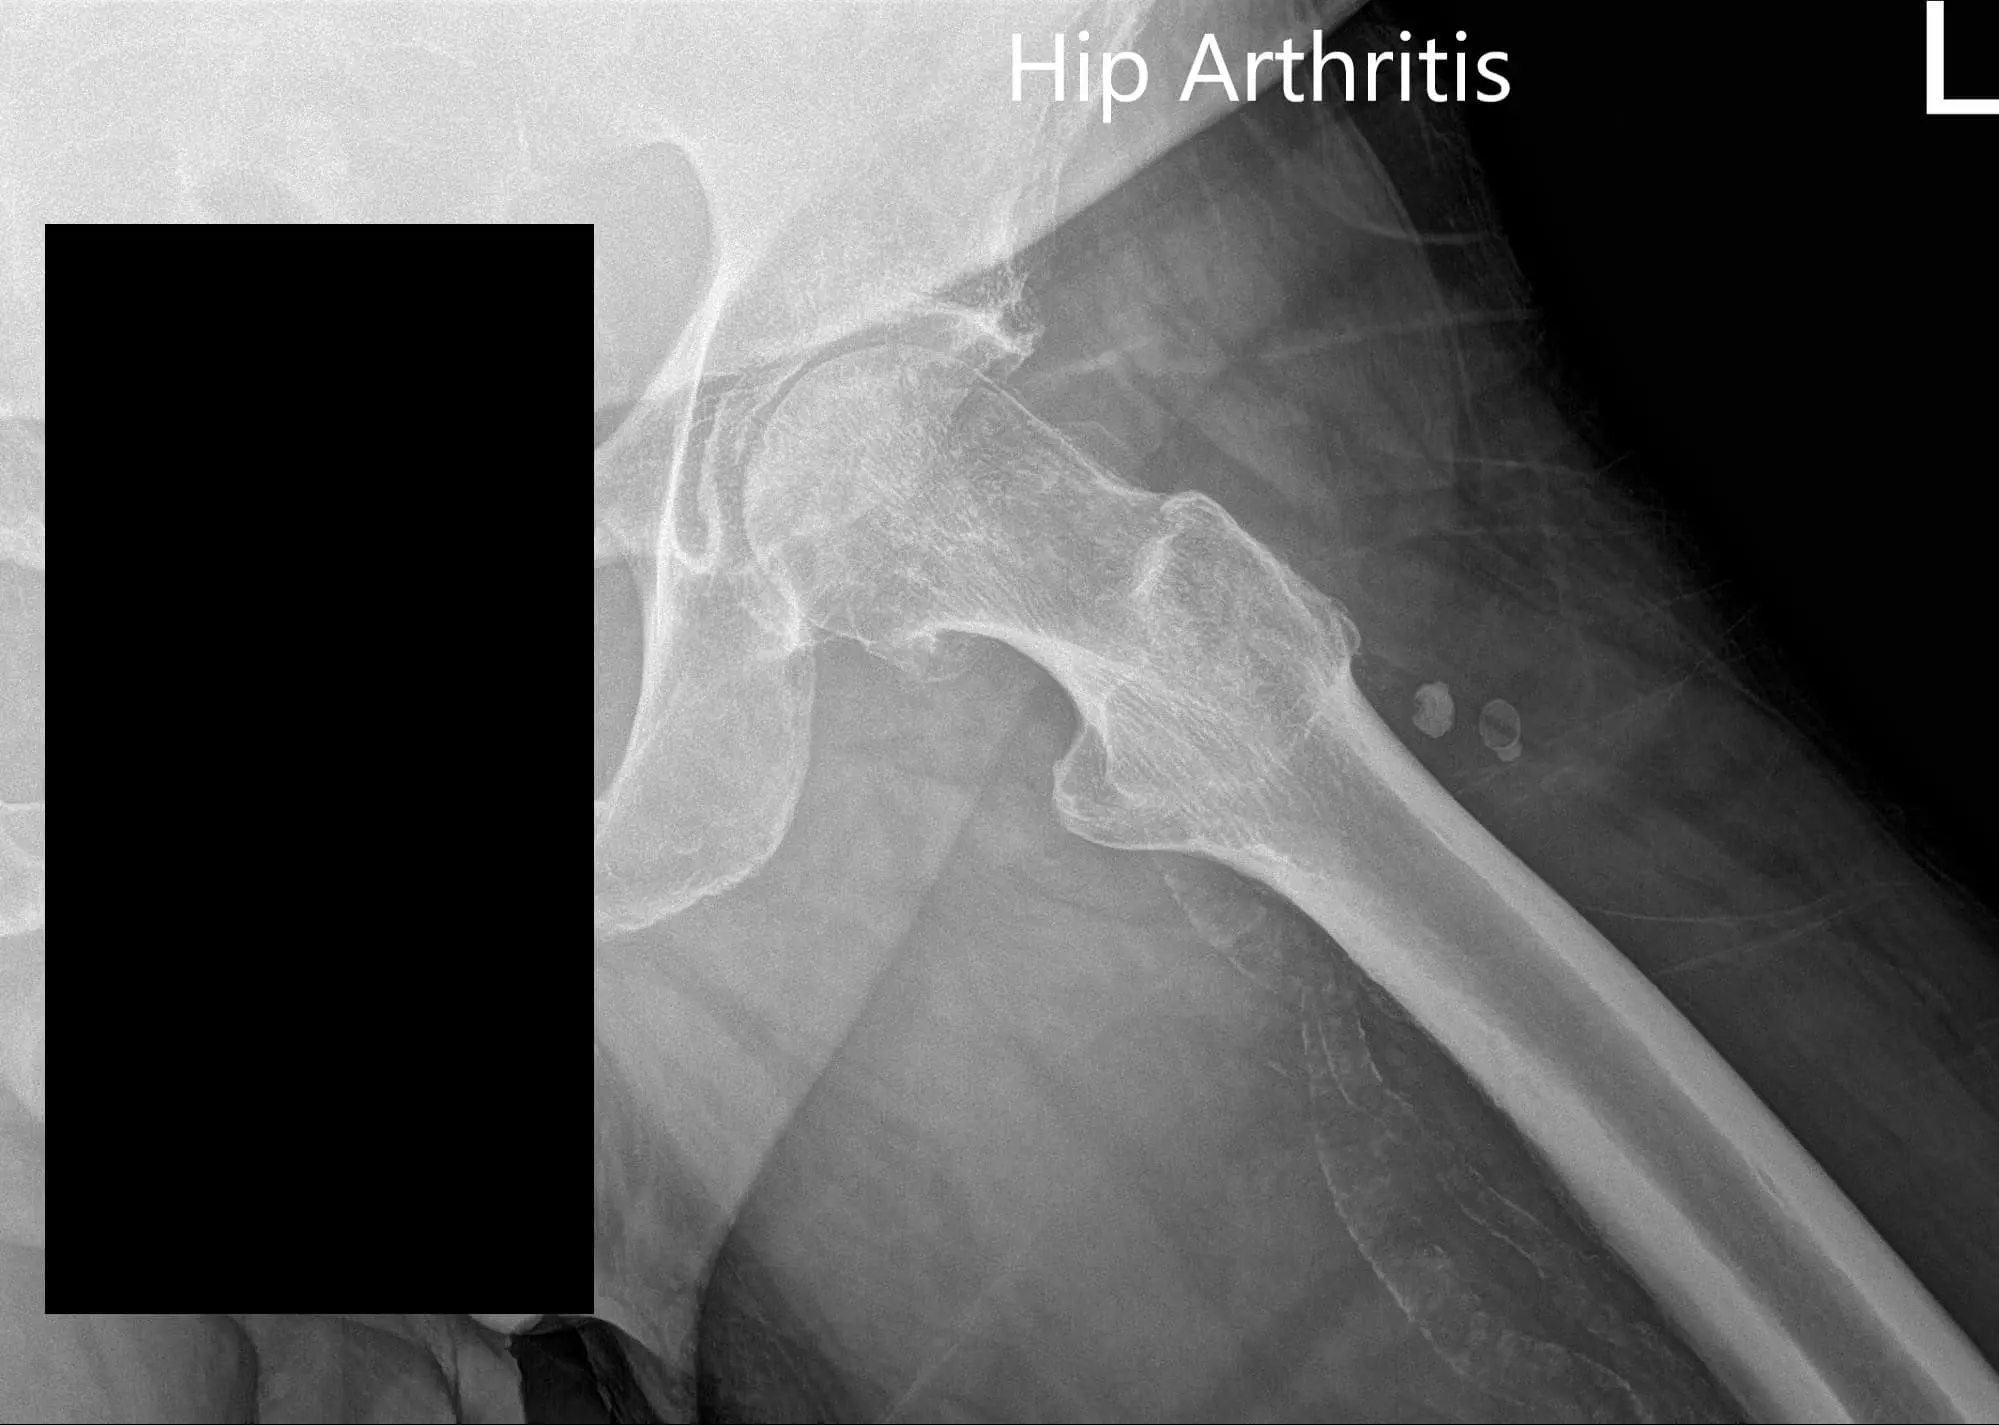

Imaging revealed severe osteoarthritis of the left hip. Considering, patients’ medical conditions and lifestyle limiting hip pain, she was advised left total hip replacement. Risks, benefits, and alternatives were discussed at length. She agreed to go ahead with the procedure.

Preoperative X-ray of the left hip showing AP and frog-legged lateral view

Preoperative X-ray of the left hip showing AP and frog-legged lateral view - img 2